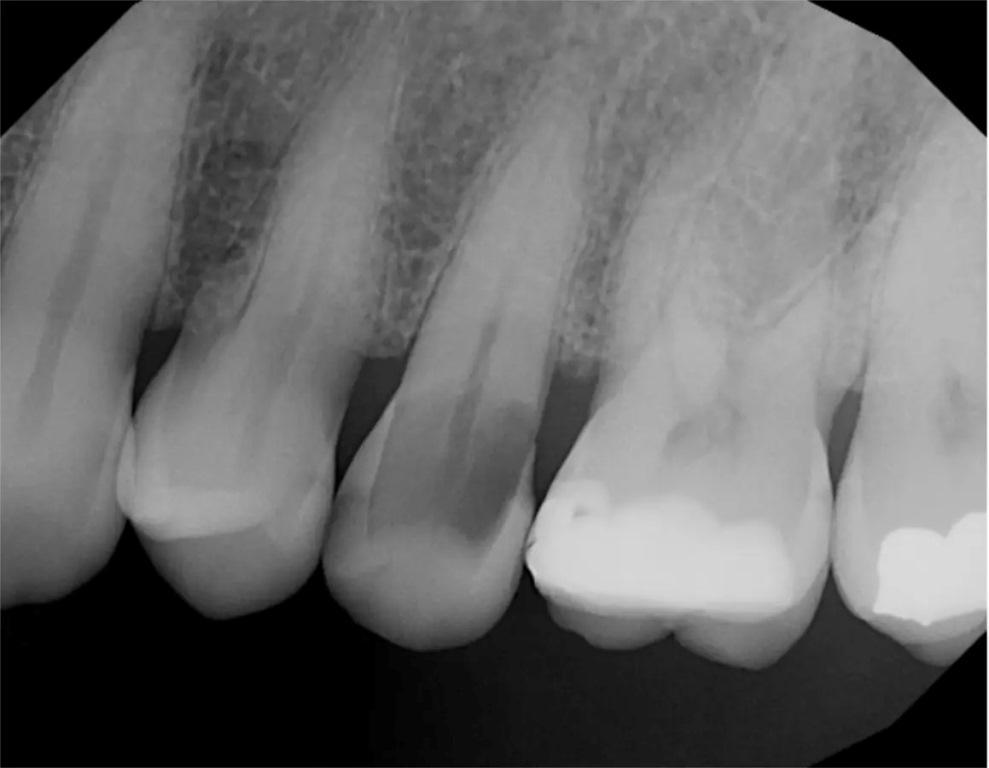

На повторном плановом профилактическом приеме через пять лет была сделана периапикальная рентгенограмма (фото 12). Как было отмечено на предыдущих контрольных рентгенограммах, периапикальная рентгенопрозрачность отсутствовала, что свидетельствует об успешном лазерном лечении в предотвращении периапикальной патологии и инфекции пульпы.

Фото 12: Периапикальная рентгенограмма, сделанная через пять лет после лазерного удаления пульпы и реставрации зуба, не выявила периапикальной патологии.